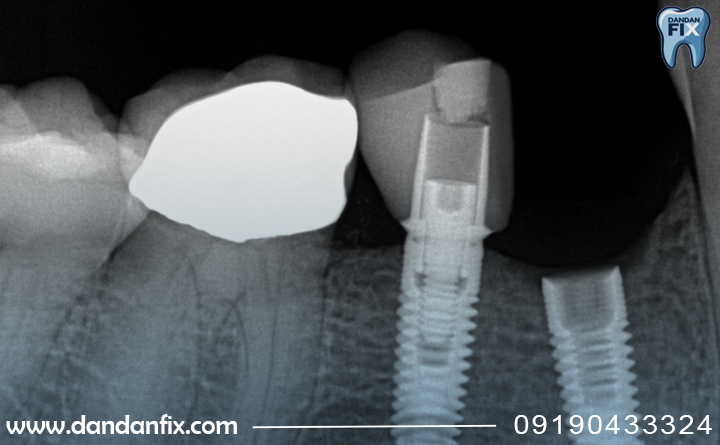

برای درمان پزشک با گرفتن عکس رادیوگرافی وضعیت استخوان را بررسی میکند. اگر جوش خوردگی ناقص باشد، معمولاً ایمپلنت خارج میشود، محل آن ترمیم شده و پس از چند ماه، پایه جدید در محل کاشته میشود.

پیش از کاشت، دندان پزشک با عکس CBCT تراکم استخوان را بررسی میکند. در صورت کمبود، پیوند استخوان (Bone Graft) یا استفاده از ایمپلنتهای کوتاهتر و ضخیمتر انجام میشود.

پزشک با عکس رادیوگرافی وضعیت استخوان، لثه و اتصالات ایمپلنت را بررسی میکند و در صورت وجود لقی یا التهاب، قبل از پیشرفت، آن را درمان میکند.